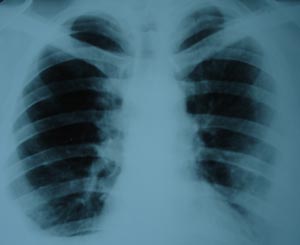

Bilateral pleural effusion

The radiological appearance of fluid in the pleural cavity are the Same regardless of its eteiology whether it is transudate, exudates, pus or blood. The underlying lung pathology may not be seen because the pleural effusion shadow is uniform & homogenous. It lies outside the lung edge & obliterates costophrenic angle. The fluid appears higher laterally than medially.In addition to the transudate pathology, one can come across bilateral pl.effusion in SLE, rheumatoid, sarcoidosis, malignancy & in immunocompromised patient.